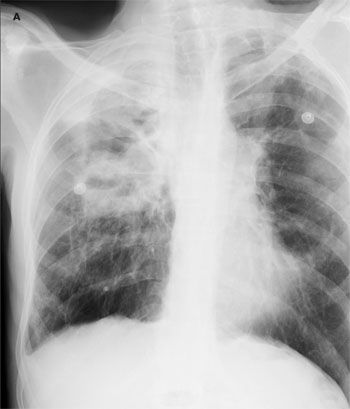

The patient was afebrile. Oxygen saturation was 99% on room air. Positive findings were dry inspiratory crackles and rhonchi in the right lung field, and a mobile, 1 x 1-cm, mildly tender right cervical lymph node. A chest radiograph revealed right apical pleural thickening involving the upper half of the right hemithorax, cavitation with an air-fluid level, emphysematous bullae, and scarring in the left upper lung (A). A CT scan of the chest showed a complex 7.6 x 6.2-cm cavity with thick and irregular walls in the right lung with volume loss and scarring (B and C). An extensive amount of heterogeneous material was located within the cavity. Scarring and bronchiectasis in the left upper lung and multiple lymph nodes (the largest, 2 x 2 cm) in the right hilum were also noted.